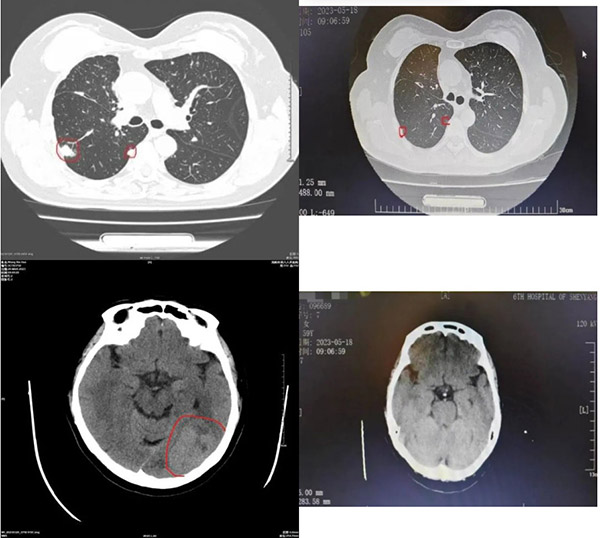

▲治疗前(左列)、后(右列)影像对比

随 着治疗深入,王女士的症状开始减轻。两个月后,复查CT显示右肺肿瘤由原来4.3cm×3.0cm缩小到0.4cm,颅内枕顶叶转移瘤由原来 5.1cm×3.0cm缩小到2.9cm×1.6cm,病情得到了有效控制。用患者和家属的话说:“这么短的时间里肿瘤缩小这么多,生活质量得到了明显提 高,可以像正常人一样生活了,真是不可思议啊!”